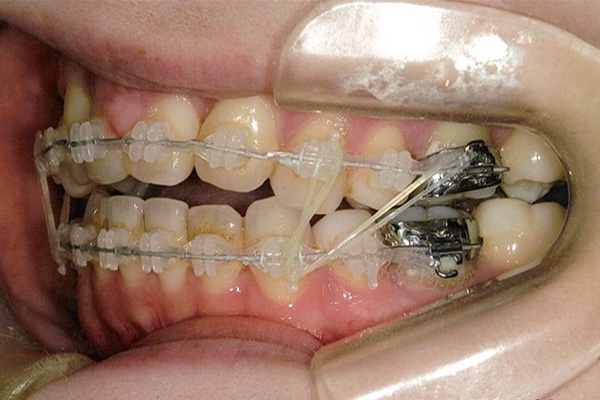

1年3ヶ月後